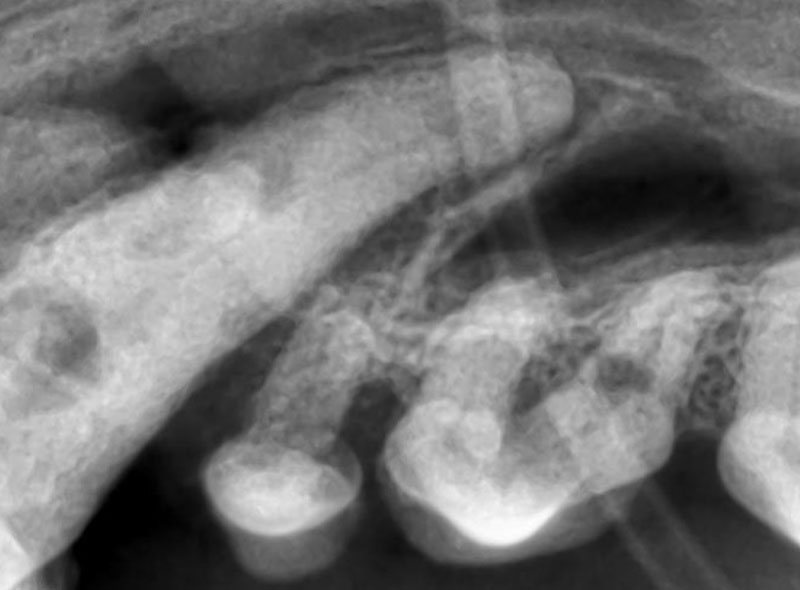

犬の吸収病巣

歯頚部が溶けています。

歯髄まで侵されると痛みを感じるため、噛むときに使わなかったり、歯磨きを嫌がるようになります。